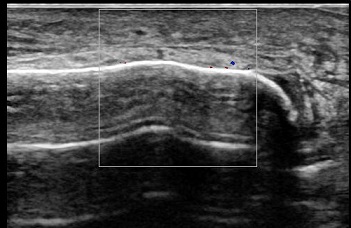

レントゲンではわかりづらい外くるぶしの骨折 よしだ整骨院

外くるぶしの骨折 エコー画像 よしだ整骨院